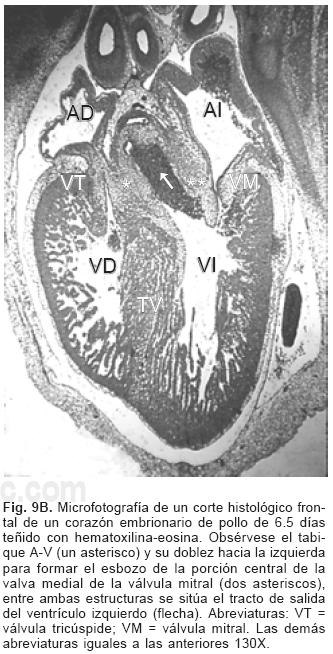

El proceso embrionario de la tabicación A–V se establece con el crecimiento y desarrollo del mesénquima cardíaco de las almohadillas endocárdicas dorsal y ventral del canal A–V que en el embrión ocurre entre los estadios (25 al 29) de Hamburguer y Hamilton17,18 (Fig. 8A), dichas almohadillas completamente desarrolladas se fusionan y conforman el tabique A–V que divide al canal A–V común en dos: derecho e izquierdo (Fig. 8B) en cuyas paredes se diferencian dos anillos fibrosos situados a desnivel, uno para la válvula tricúspide y otro para la válvula mitral (Fig. 9A). El extremo craneal de este tabique se dobla hacia la izquierda, crece dentro del canal A–V izquierdo y se transforma en el esbozo de la porción central de la valva medial (aórtica) de la válvula mitral21 (Fig. 9B), proceso que ocurre en los embriones humanos en los horizontes de Streeter del XIII al XVI.19,20 El espacio comprendido entre el tabique ventricular y la valva medial de la válvula mitral constituye el tracto de salida del ventrículo izquierdo. La valva lateral de la válvula mitral se separa como un faldón de la pared del canal A–V y del ventrículo izquierdo del que se diferencian también sus cuerdas tendinosas y músculos papilares (Fig. 9B). La válvula tricúspide se desarrolla por el mismo proceso de delaminación para conformar tres láminas de miocardio que corresponden a las valvas septal, anterior y posterior con sus respectivas cuerdas tendinosas y músculos papilares.1

La rama derecha del tabique A–V embrionario origina al tabique A–V definitivo cuyo mesénquima se transforma en músculo, el extremo anterosuperior del mismo se diferencia en el tabique membranoso del corazón (Fig. 9B).22 La porción de entrada del tabique ventricular se fusiona con la rama derecha del tabique A–V, lo que oblitera la comunicación interventricular de la porción de entrada.